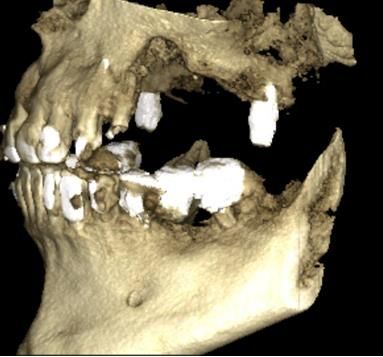

Figure 3

Volumetric modeling based on computed tomography of patient Y before surgery

On cone beam computed tomography, the presence of a defect in the alveolar process of the upper jaw on the left at the level of missing 24-26 teeth with transition to the anterior maxillary sinus and the cheek-alveolar ridge is determined. The sinus is made of homogeneous contents. (Fig. 1,2,3).